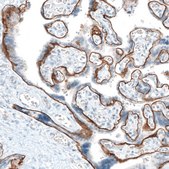

Monoclonal Anti-ITGA6 antibody produced in mouse

IHC

immunohistochemistry: 1:500-1:1000

All Prestige Antibodies Powered by Atlas Antibodies are developed and validated by the Human Protein Atlas (HPA) project and as a result, are supported by the most extensive characterization in the industry. The Human Protein Atlas project can be subdivided into three efforts: Human Tissue Atlas, Cancer Atlas, and Human Cell Atlas. The antibodies that have been generated in support of the Tissue and Cancer Atlas projects have been tested by immunohistochemistry against hundreds of normal and disease tissues and through the recent efforts of the Human Cell Atlas project, many have been characterized by immunofluorescence to map the human proteome not only at the tissue level but now at the subcellular level. These images and the collection of this vast data set can be viewed on the Human Protein Atlas (HPA) site by clicking on the Image Gallery link. We also provide Prestige Antibodies® protocols and other useful information.

• IHC tissue array of 44 normal human tissues and 20 of the most common cancer type tissues.